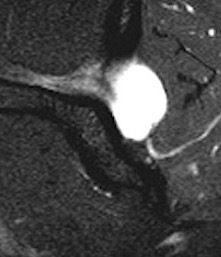

MRI

Spinoglenoid cyst

Spinoglenoid cyst with SLAP tear and posterosuperior labral tear